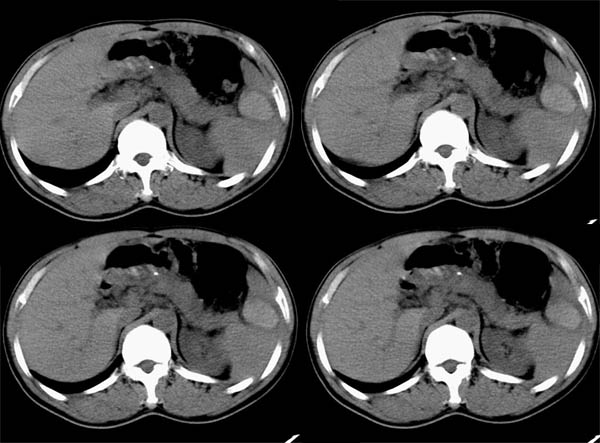

m50y以腹疼、腹胀2小时就诊。腹透肠胀气较明显,余无明显异常。做ct时腹疼已明显缓解;病人否认外伤史,否认血液病变、否认肝炎史。建议第二天做ct增强,病人第二天放弃了增强。脾脏区较高密度影ct值为60hu,正常脾脏ct值为45hu(窗宽:150,窗位:56)。

脾区病变局部2mm重建:

ct表现:脾脏内见较高密度影ct值为60hu,正常脾脏ct值为45hu(窗宽:150,窗位:56)。 边界清晰,周围见略低密度影

脾脏实质内高密度病变,ct值为60hu,边界清晰,无明显外伤病史,腹痛、腹胀2小时就诊,首先考虑脾脏血管瘤破裂出血。